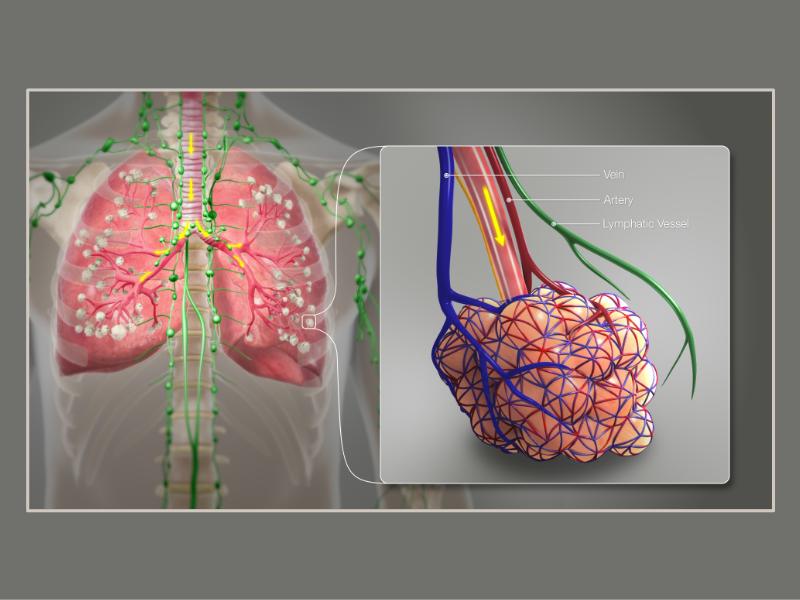

Transitions

Bronchi - Transitions

- Intrapulmonary bronchi

- Irregular cartilage

- Respiratory epithelium

- Glands

- Bronchioles

- Smooth muscle REPLACE cartilage

- Ciliated columnar > Ciliated cuboidal

- NO glands - goblet cells -> secretory cells

- Terminal bronchioles

- Smooth muscle

- Ciliated cuboidal epithelium

- Secretory cells

- Respiratory bronchioles

- Conducting -> Respiratory

- Simple cuboidal epithelium

- Secretory cells

- Alveoli

Lungs